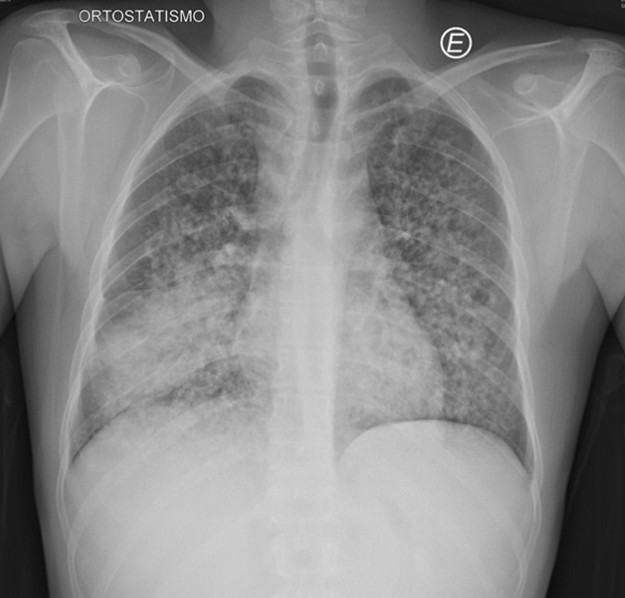

A chest radiograph (Figure 1) and a thoracic computed tomography (CT) were performed, revealing multiple bilateral solid and subsolid nodules, ill-defined and with varying sizes (not exceeding 1 cm), with a tendency to confluence and mostly with a peribroncovascular pattern of distribution, although some juxta-pleural nodules were seen (Figure 2). Additionally, a consolidation on the middle and right lower lobe with air-bronchogram was identified (Figure 2). Multiple enlarged mediastinal and hilar lymph nodes were also present, some with central hypodensity suggestive of necrosis (Figure 3). Pleural effusion was excluded.

Figure 1: Chest radiograph showing an airspace consolidation with air bronchogram in the right lower hemithorax, associated with multiple and bilateral nodules.